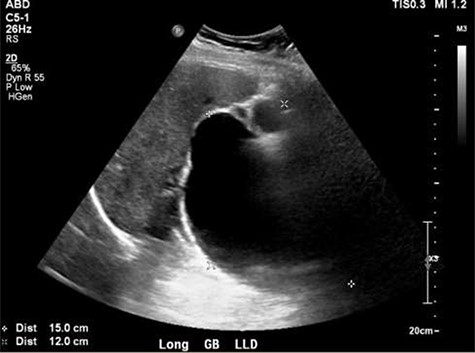

Ultrasound showing obscured CBD, 3 mm gallbladder wall, and a cystic lesion communicating with the CBD and a large gallbladder cyst.

A right upper quadrant abdominal ultrasound was obtained which showed that the gallbladder wall was 3 mm, an obscured common bile duct (CBD), and a cystic lesion communicating with the CBD and a large gallbladder cyst (Fig. 2). A contrast MRI with magnetic resonance cholangiopancreatography (MRCP) of the abdomen revealed marked fusiform dilatation of the extrahepatic CBD measuring 8.8 cm anterior–posterior x 10.9 cm transverse x 12.7 cm craniocaudally, mild-to-moderate central intrahepatic bile duct dilatation and posterior displacement of the patent main portal vein due to associated mass effect (Fig. 3). Based on the image findings the diagnosis of a CC was made. The type, however, could not be definitively diagnosed as the cyst could be a large type I CC with resultant upstream intrahepatic ductal dilatation versus a type IVa CC with associated mild to moderate central intrahepatic biliary ductal dilatation. Upon review of the images, labs, assessment of the patient, she was scheduled for resection of the extra hepatic bile duct and choledochal cyst with planned Roux en y hepaticojejunostomy. Intraoperatively, she was found to have a massive 20 cm type I choledochal cyst (Fig. 4).